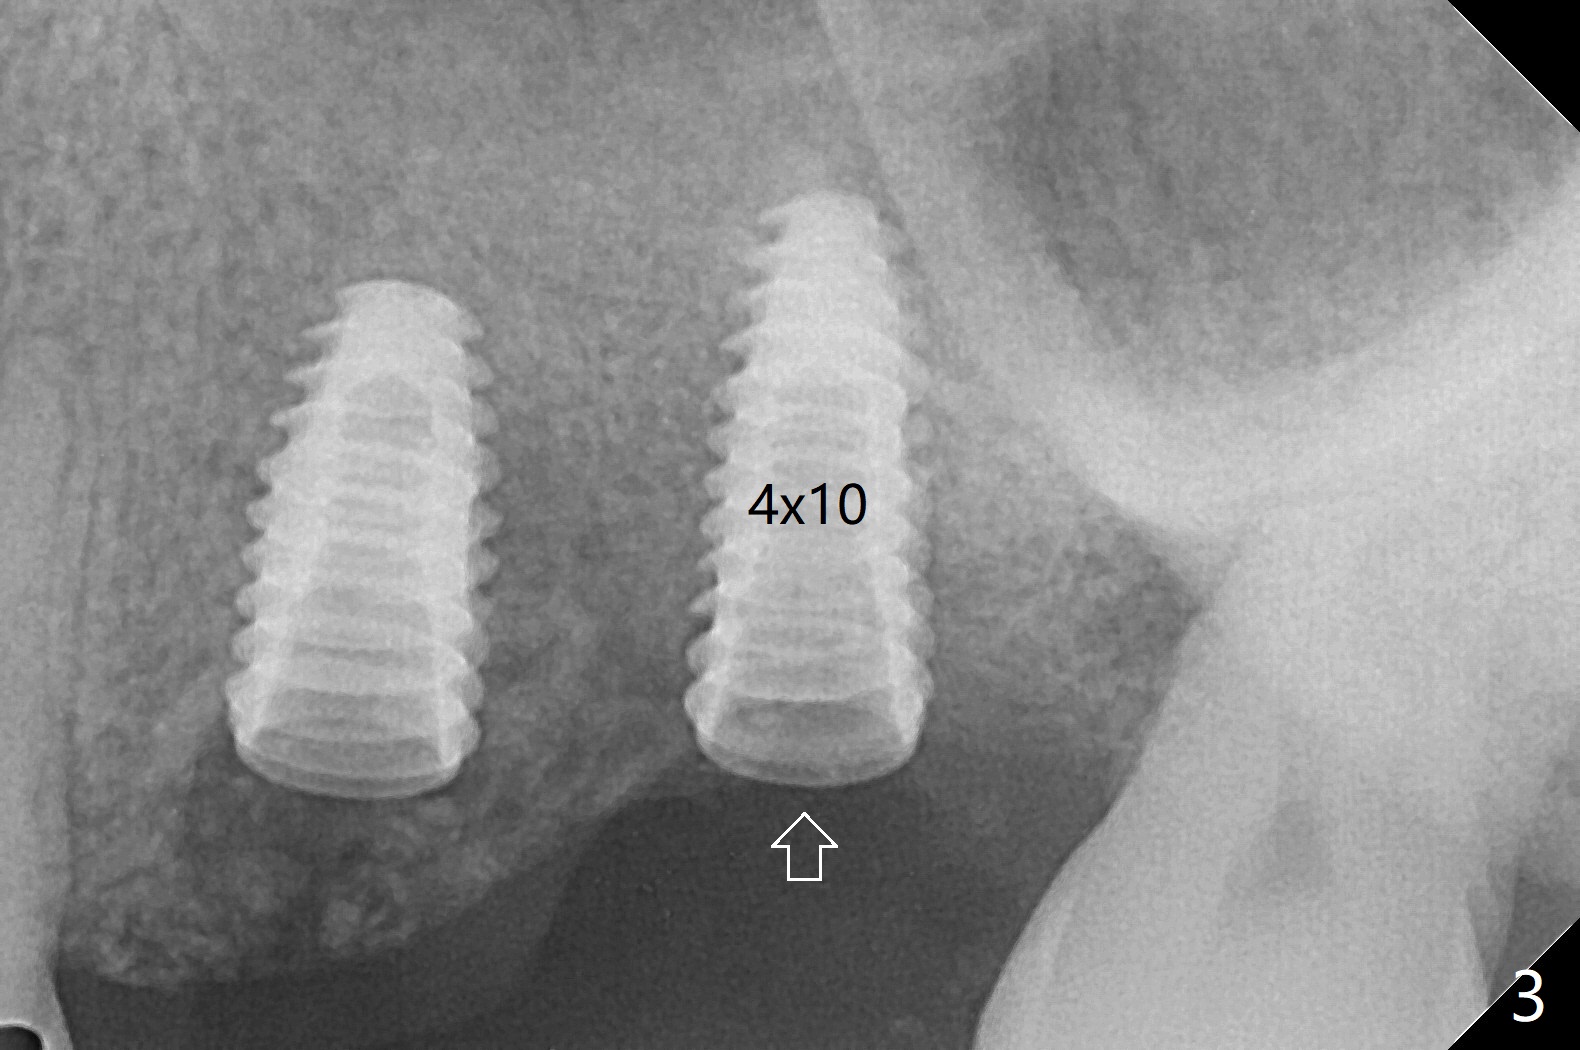

左上六植牙第三次失败后五个月,牙槽嵴宽度尚可,切开后放置导板,3.2乘19毫米园钻头好像接近上颌窦底板(图一),但是粘性骨块和4乘10毫米报废植体就不能进入上颌窦(图二),最后不得不使用3毫米Bicon骨凿,之后同一个报废植体就似乎进入上颌窦(图三),4.5乘8.5毫米正式植体植入深度和稳定性均正常(图四),腭侧植体稍微暴露,放置愈合螺丝后,放置骨粉和PRF膜,缝合,左上5植体放置5.7x4.5(4)毫米基台,固定牙周敷料。术后5.5个月植体好像整合(图五),缺牙间隙特别小,5临时牙冠(P)必须取出才能切开暴露植体,放置5.5x5毫米愈合基台(图六)。伤口愈合后,必须做渐进性负荷,之后做简单局部矫正,推7往远中,6缺失3年,7往近中倾斜移位。两周后牙周敷料脱落,伤口愈合,放置修复基台,故意将基台平面朝远中,足够空间制作临时牙冠(图七)。调整基台长度(比较图七,八)。制作连体牙冠(5,6),有意提高5牙冠高度,使左上7不与对合牙接触,有利于远中移位(图九)。也要在对侧提高咬合(图十)。局部矫正一个月后,磨去右侧咬合垫和磨短左上5,6临时牙冠,前牙还不能完全接触(图十一)。1-2星期前牙开合自行消失,取模做左上5,6牙冠。局部矫正似乎使左上7远中移位大约3毫米(比较图十二,十三)。粘固拧紧后(20 Ncm)14号牙牙冠咬合增高,拍摄根尖片(图十三),两个基台好像仍然完全就位,然后调整咬合。